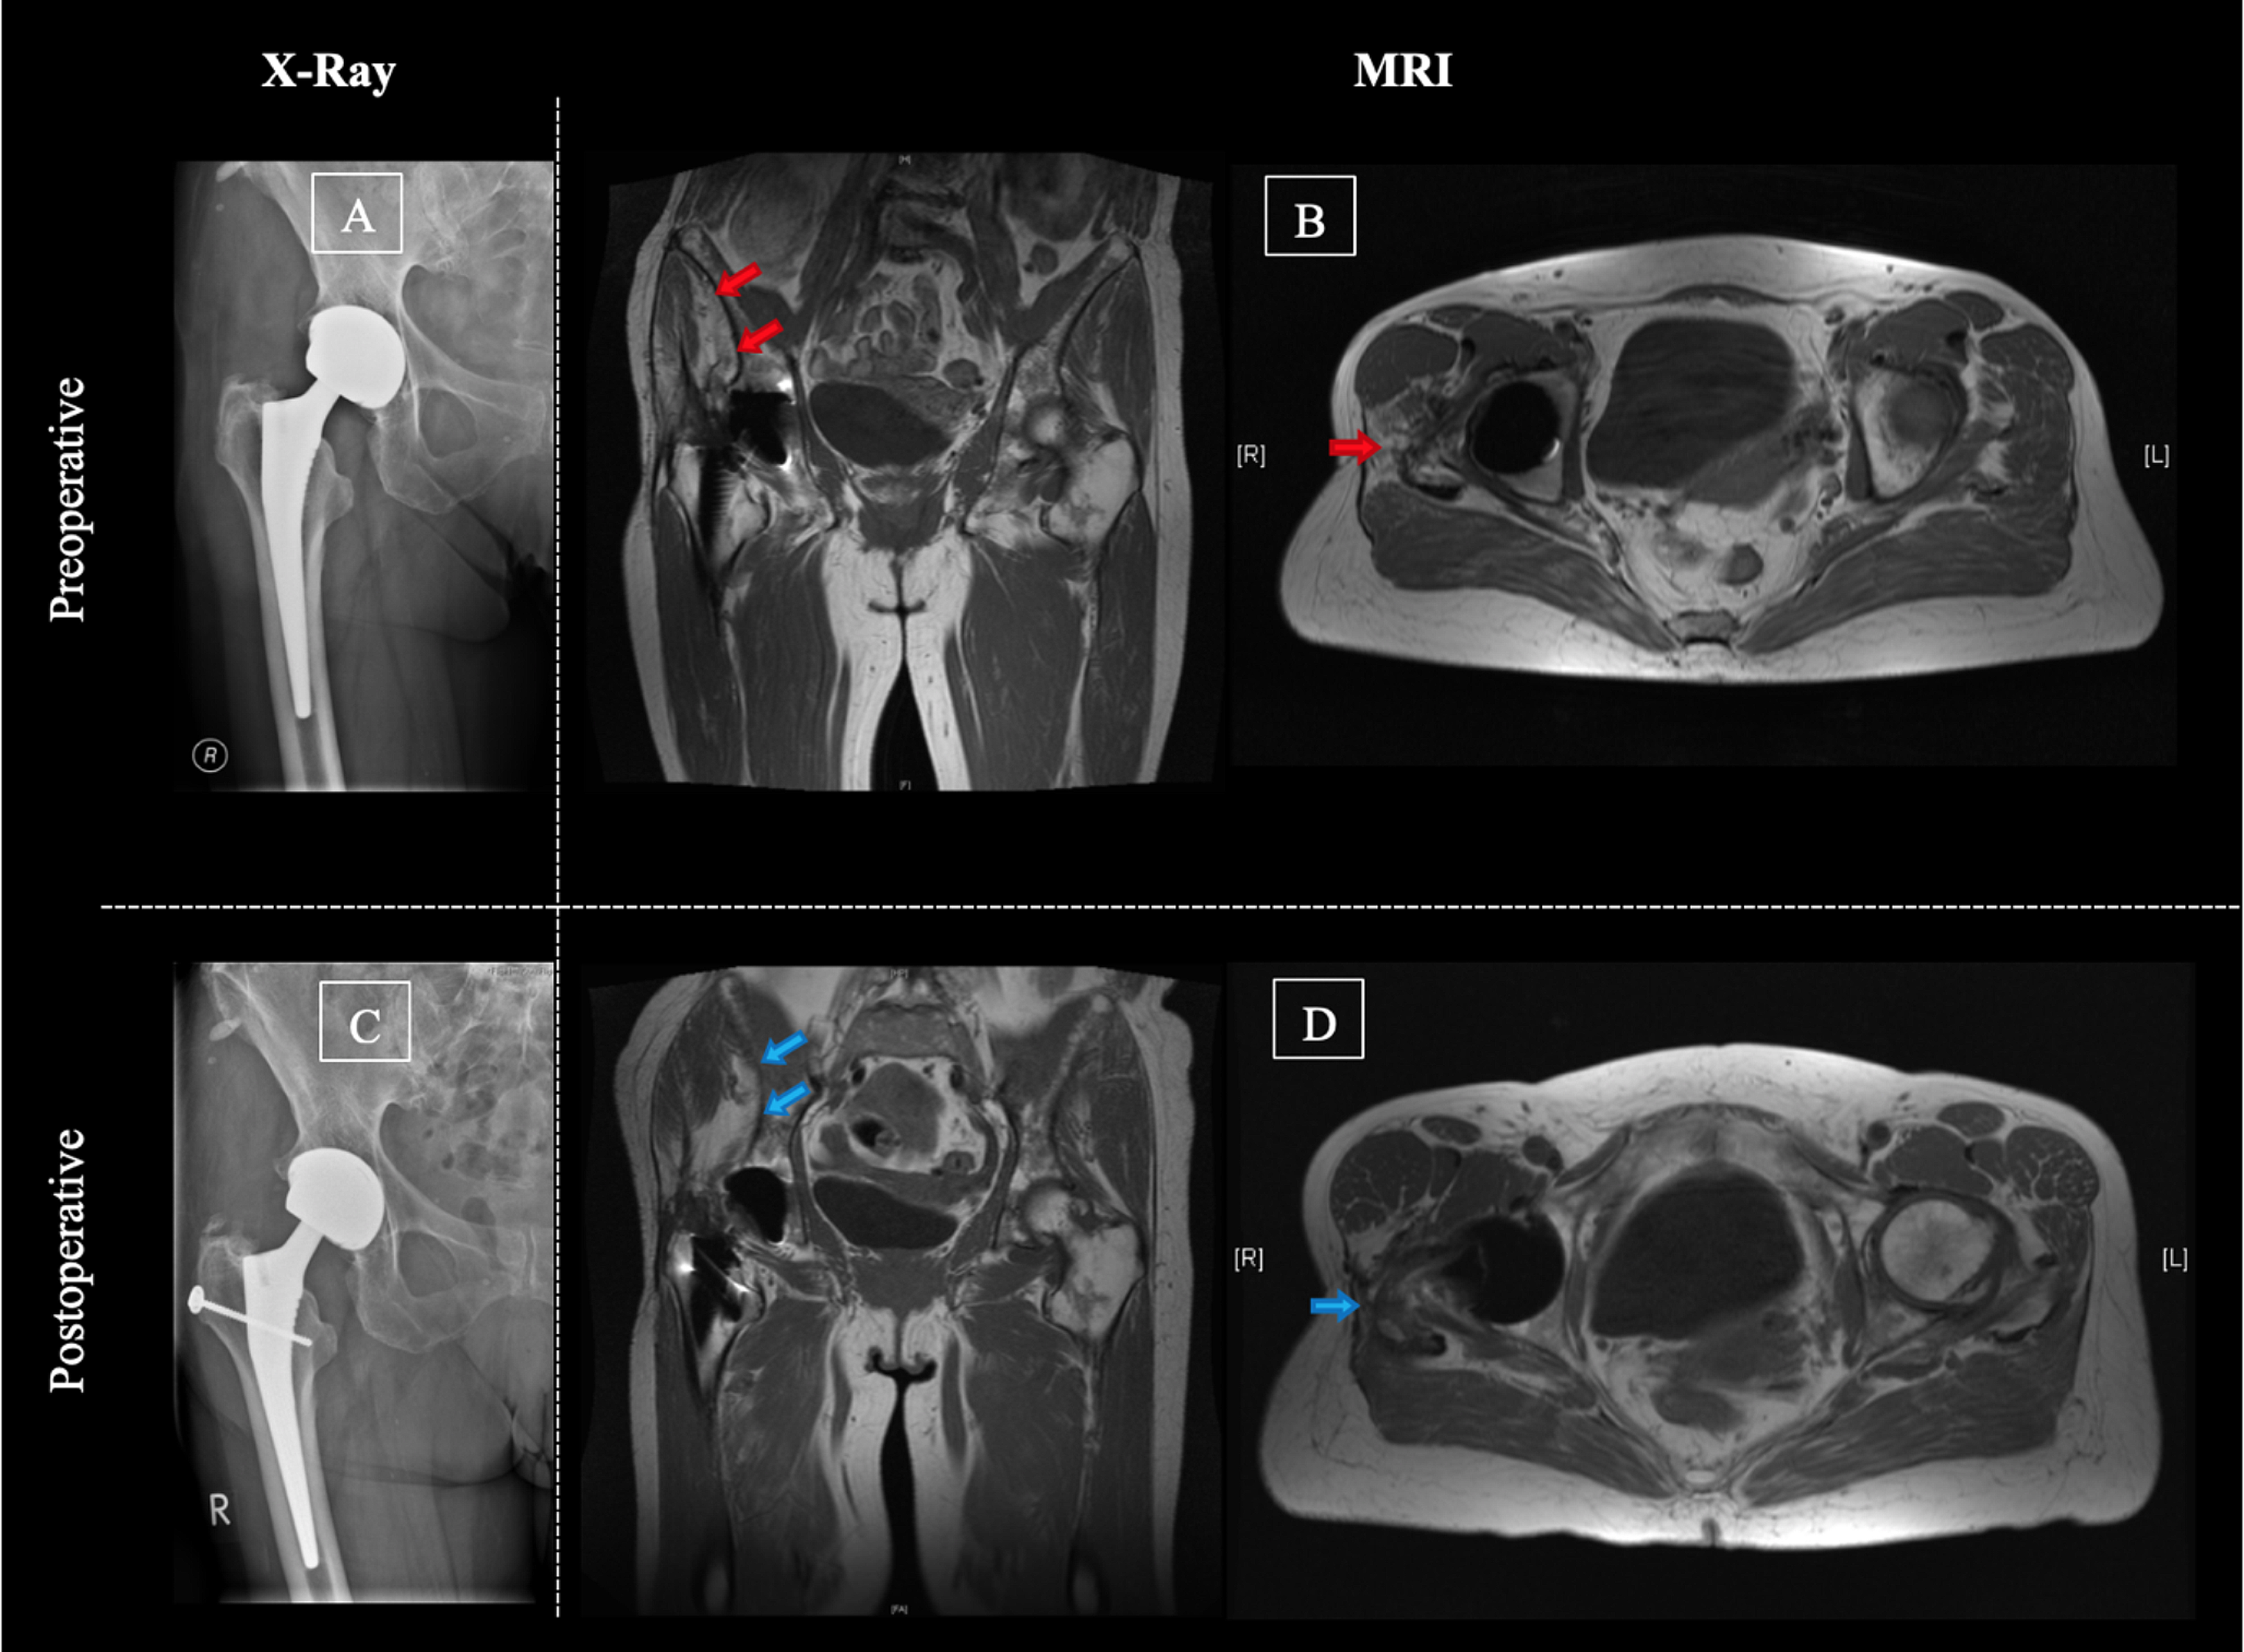

MRI scans were performed pre- and postoperatively. The total muscle volume, the volume of fatty degenerated muscular tissue, the lean muscle volume (total volume minus fat ratio) and the level of muscular degeneration after the Goutallier classification (G1-G4) were evaluated. All investigations were assessed by a musculoskeletal trained radiologist and an experienced orthopedic surgeon (K.T. and G.E.). Measurements were performed pre- and postoperatively for the following muscles: gluteus minimus (Gmin), gluteus medius (Gmed), gluteus maximus (Gmax) and tensor fascia lata muscle (TFL). The muscle flap size was included in the Gmax volume postoperatively (Fig. 1).

Fig. 1

Example and illustration of MRI measurements of the gluteal muscles. Preoperative (A and B) and postoperative (C and D) MR images after gluteus maximus flap transfer. Measurements regarding the level of degeneration (A and C, Goutallier IV) and the total muscle volume (B and D) of the gluteus medius muscle of a 64-year-old patient with chronic abductor mechanism deficiency on the right hip joint after total hip arthroplasty. To receive volumetric results, measurements were performed in slides of the MR image pre- and postoperatively and were highlighted for the gluteus medius muscle in this figure (B and D)

Leo A. Whiteside published and step-by-step illustrated the surgical technique of the gluteus maximus transfer in 2012 [18]. The technique describes a Gmax flap transfer to compensate for a degenerative modified Gmed and Gmin muscle. Therefore, the gluteus maximus muscle is split in the direction of the muscle fibers towards the fascia latae. This part of the elevated gluteus maximus muscle gets then divided in two flaps. The posterior flap is placed over the femoral neck toward the anterior joint capsule. The anterior flap is positioned directly on the femur distal of the greater trochanter [18]. In our series, the surgical technique for the gluteus maximus flap transfer was marginally modified. Accordingly, a screw and a transosseous fixation was used to fix the tendinous part of the anterior flap distal of the greater trochanter (Fig. 2).

Fig. 2

Example of pre- and postoperative radiographic evaluation. Pre- (A and B) and postoperative (C and D) X-ray and MRI images of a 69-year-old patient treated with a gluteus maximus muscle flap due to an abductor mechanism deficiency. Preoperatively, a significant degeneration of the gluteus medius muscle (red arrows) was seen without signs of component loosening or infection. The postoperative radiographic images present the screw that was used to fix the anterior flap on the proximal femur (C). The postoperative MRI shows no significant further loss of volume or degeneration of the gluteus medius muscle as well as no flap necrosis (D, blue arrows)